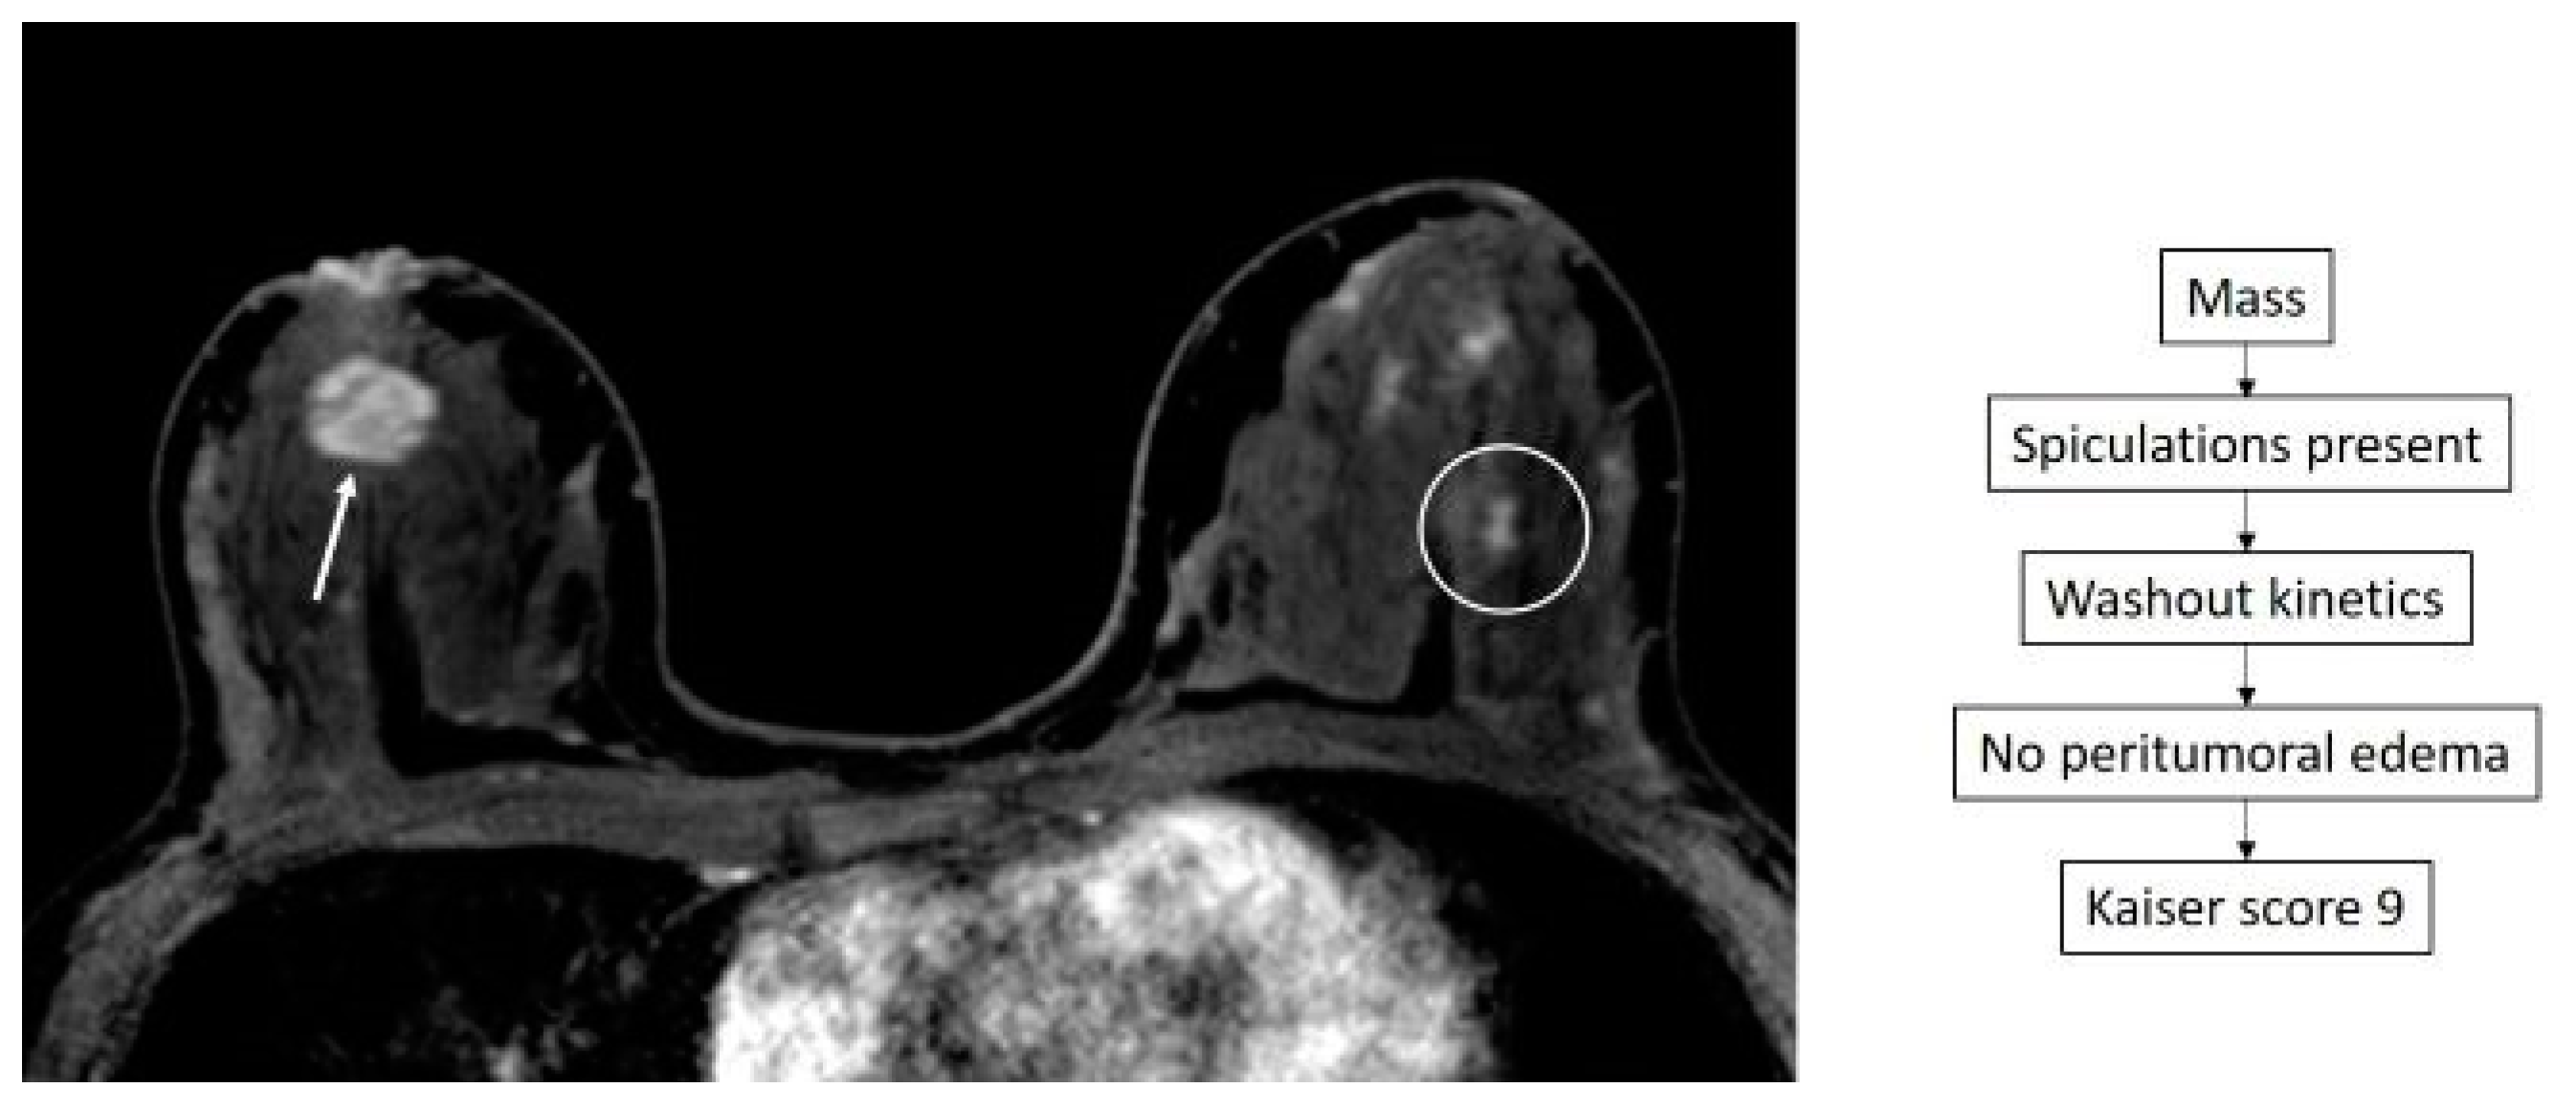

- Dietzel, M.; Baltzer, P.A.T. How to Use the Kaiser Score as a Clinical Decision Rule for Diagnosis in Multiparametric Breast MRI: A Pictorial Essay. Insights Imaging 2018, 9, 325–335. [Google Scholar] [CrossRef] [PubMed]

- Baltzer, P.A.T.; Krug, K.B.; Dietzel, M. Evidence-Based and Structured Diagnosis in Breast MRI Using the Kaiser Score. ROFO. Fortschr. Geb. Rontgenstr. Nuklearmed. 2022, 194, 1216–1228. [Google Scholar] [CrossRef]